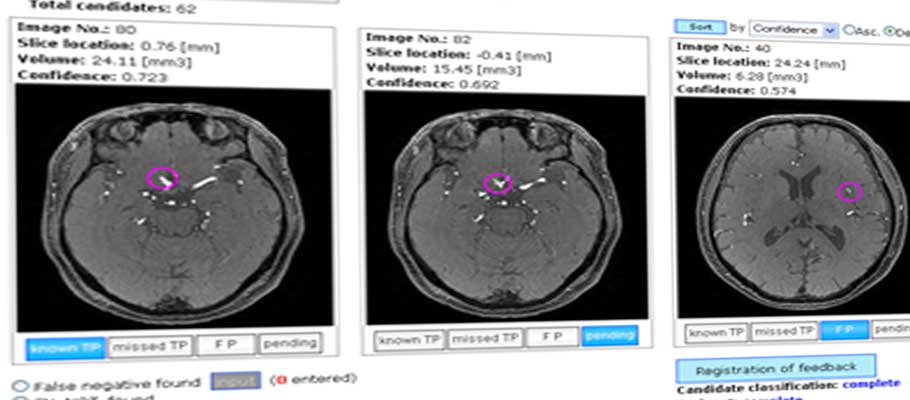

脳動脈瘤自動検出

深層学習を用いて精度を向上